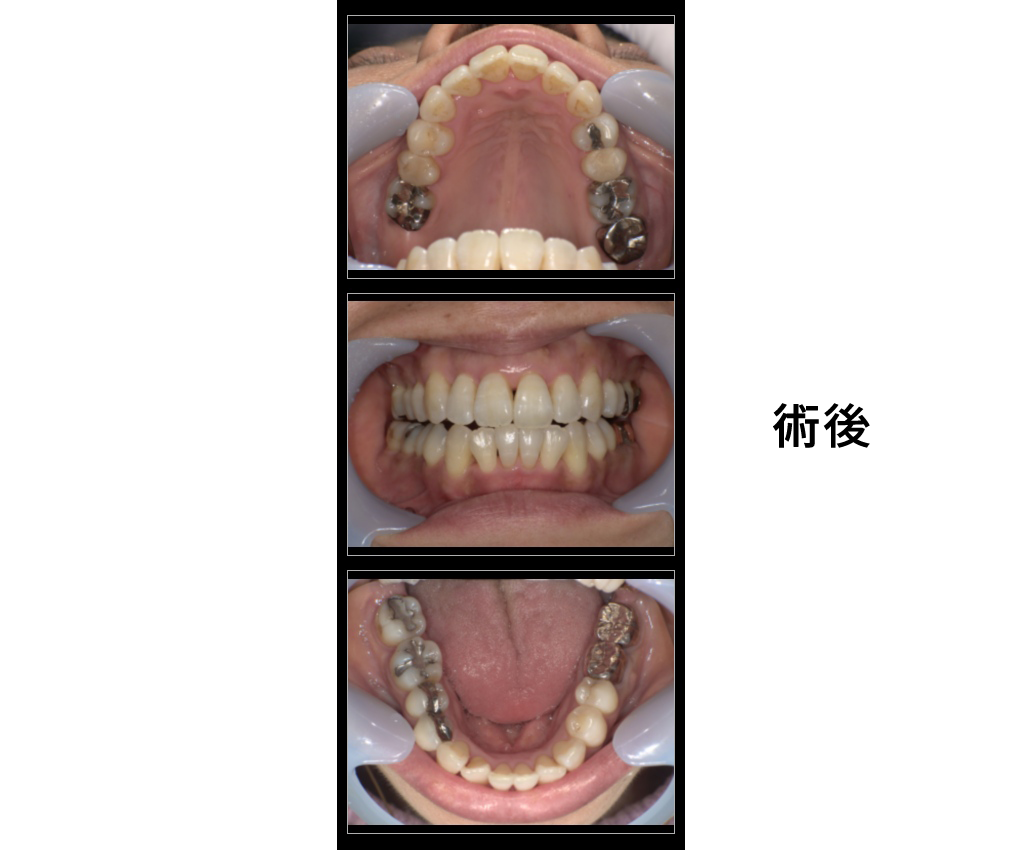

女性50歳

治療内容:定期検診希望だが歯並びが気になる

→歯周治療後にインビザラインGOにて矯正治療

金額:診断22000円、矯正440000円

来院理由:全体的に診てほしい

施術の副作用(リスク):

痛みや違和感を感じることがあります。歯が一時的に動揺することがあります。

咬みにくさをかんじることがあります。